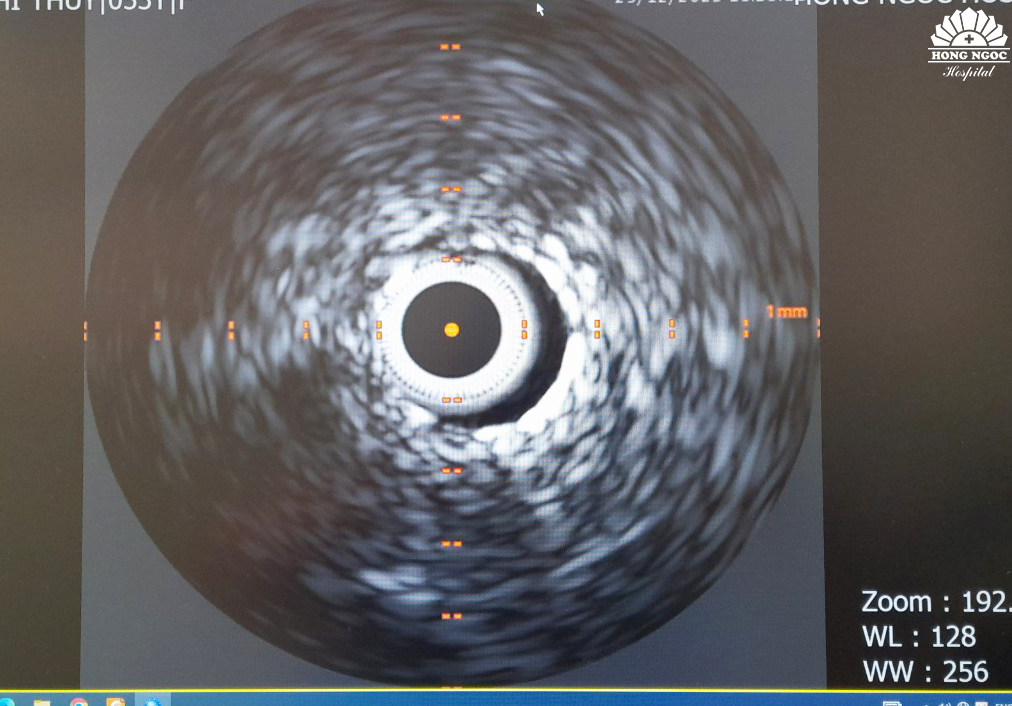

Sau can thiệp, kỹ thuật siêu âm trong lòng mạch (IVUS) tiếp tục được sử dụng để theo dõi kết quả, xem stent đã phủ hết được phần lóc tách hay chưa.

Theo BS.Công: “Với kỹ thuật siêu âm trong lòng mạch IVUS, chúng tôi có thể đánh giá chính xác mức độ thành công của ca bệnh. Bên cạnh việc hỗ trợ thực hiện đưa stent vào và đặt stent chính xác tại vị trí tổn thương, hình ảnh siêu âm trong lòng mạch cũng giúp quan sát chính xác stent đã phủ kín phần bị lóc tách hay chưa để điều chỉnh phù hợp. Nhờ đó, hạn chế tối đa nguy cơ tái hẹp và tử vong sau can thiệp”.

Kết quả chụp mạch vành và siêu âm trong lòng mạch cho thấy stent đã phủ kín toàn bộ đoạn mạch bị lóc tách, dòng chảy mạch vành khơi thông tốt, ca can thiệp được thực hiện thành công. Sau 3 ngày nằm viện, tình trạng bệnh nhân N.T.Hà ổn định và được xuất viện.